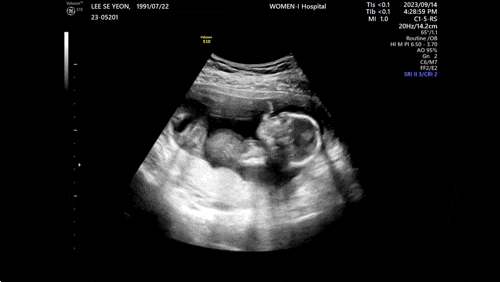

임신기록 ~28주 입체초음파